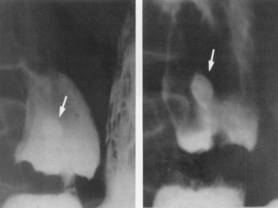

Ulcere duodenal :

Sa incidence est quatre fois de plus que ulcere gastrique

, l'homme est le plus souvent que la femme et na pas de risque

de degenerescence . Image radiologique TOGD un ulcere

duodenal aigue est une niche ronde , ovalaire remplir

de baryte , a entoure par une oedeme peri

lesionelle . Selon a la chronicite , aspect

radiologique des ulceres peuvent se deforme de images en queue de hirondelle ,

a

deux ailes , en chapeau ou en treffle ..

Aspect un ulcere jeune du

duodenum en TOGD mono contrast baryte avec

compression dosee . Image une niche ovalaire

remplisage par baryte avec etat oedemateuse de la

muqueuse peri lesionaire |

Deformation en treffle

un ulcere bulbaire |